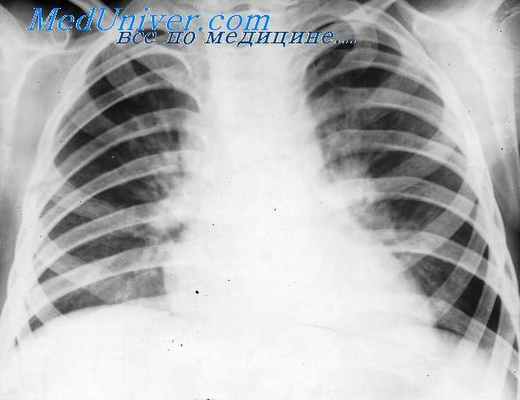

Рентгенологическое проявление лимфогрануломатоза средостения обусловлено главным образом следующими факторами: локализацией, количеством, размером пораженных лимфатических узлов и отношением их к соседним органам. Остальные рентгенологические признаки: форма, интенсивность, структура и подвижность патологической тени в основном определяются этими же факторами. Поскольку бесчисленны возможности сочетания и вариации всех перечисленных признаков, постольку многообразны рентгенологические проявления медиастинальной формы лимфогрануломатоза. В равной мере это относится и ко всем другим патологическим процессам в средостении.

В подавляющем большинстве случаев в средостении поражаются передние медиастинальные и перитрахеобронхиальные лимфатические узлы. Так, из 22 наших больных передние медиастинальные лимфатические узлы были поражены у 13, а перитрахеобронхиальные — у 9 человек. Таким образом, патологическая тень, обусловленная увеличенными лимфатическими узлами, как правило, располагается в переднем средостении. Это обстоятельство дало основание З. В. Манкину выдвинуть положение о том, что локализация патологической тени в заднем средостении с большей вероятностью говорит против лимфогрануломатоза. Однако иногда при значительном увеличении лимфатических узлов последние достигают и заднего средостения.

Помимо медиастинальных, в процесс нередко вовлекаются и бронхопульмональные лимфатические узлы, что накладывает свой отпечаток на рентгенологическую картину медиастинального лимфогрануломатоза. По данным Л. В. Фунштейна, одновременное поражение медиастинальных и бронхопульмональных лимфатических узлов встречается в 29,6% случаев, а по данным Пирса, Джекокса и Хильдрета, составляет 20,7% от общего количества больных с локализацией лимфогрануломатоза в средостении. Примерно такое же соотношение наблюдали и мы.

Вопрос о расположении увеличенных лимфатических узлов по отношению к средней линии не получил своего окончательного разрешения. Так, Ленк и Твайнинг считают, что при лимфогрануломатозе поражение лимфатических узлов средостения почти всегда бывает двусторонним.

С. И. Волков, В. А. Фанарджян, Бредфорд, Мехон и Гроу не отрицают возможности и односторонней локализации увеличенных лимфатических узлов в начальной стадии заболевания. Лишь один 3. В. Манкин полагает, что лимфогрануломатоз в большинстве случаев начинается с одной стороны средостения и переходит на другую сторону значительно позднее.

Из 22 наших больных у 15 была двусторонняя, а у 7— односторонняя локализация патологического процесса. Односторонность локализации может сохраняться в течение 3—4 лет и более (3 наших больных). В случаях двустороннего расположения патологическая тень чаще бывает асимметричной.

Соответственно расположению передних медиастинальных и перитрахеобронхиальных лимфатических узлов, чаще всего поражаемых при лимфогрануломатозе, патологическая тень обычно занимает верхнюю половину средостения, реже она распространяется на весь длинник переднего средостения или только на среднюю треть его.